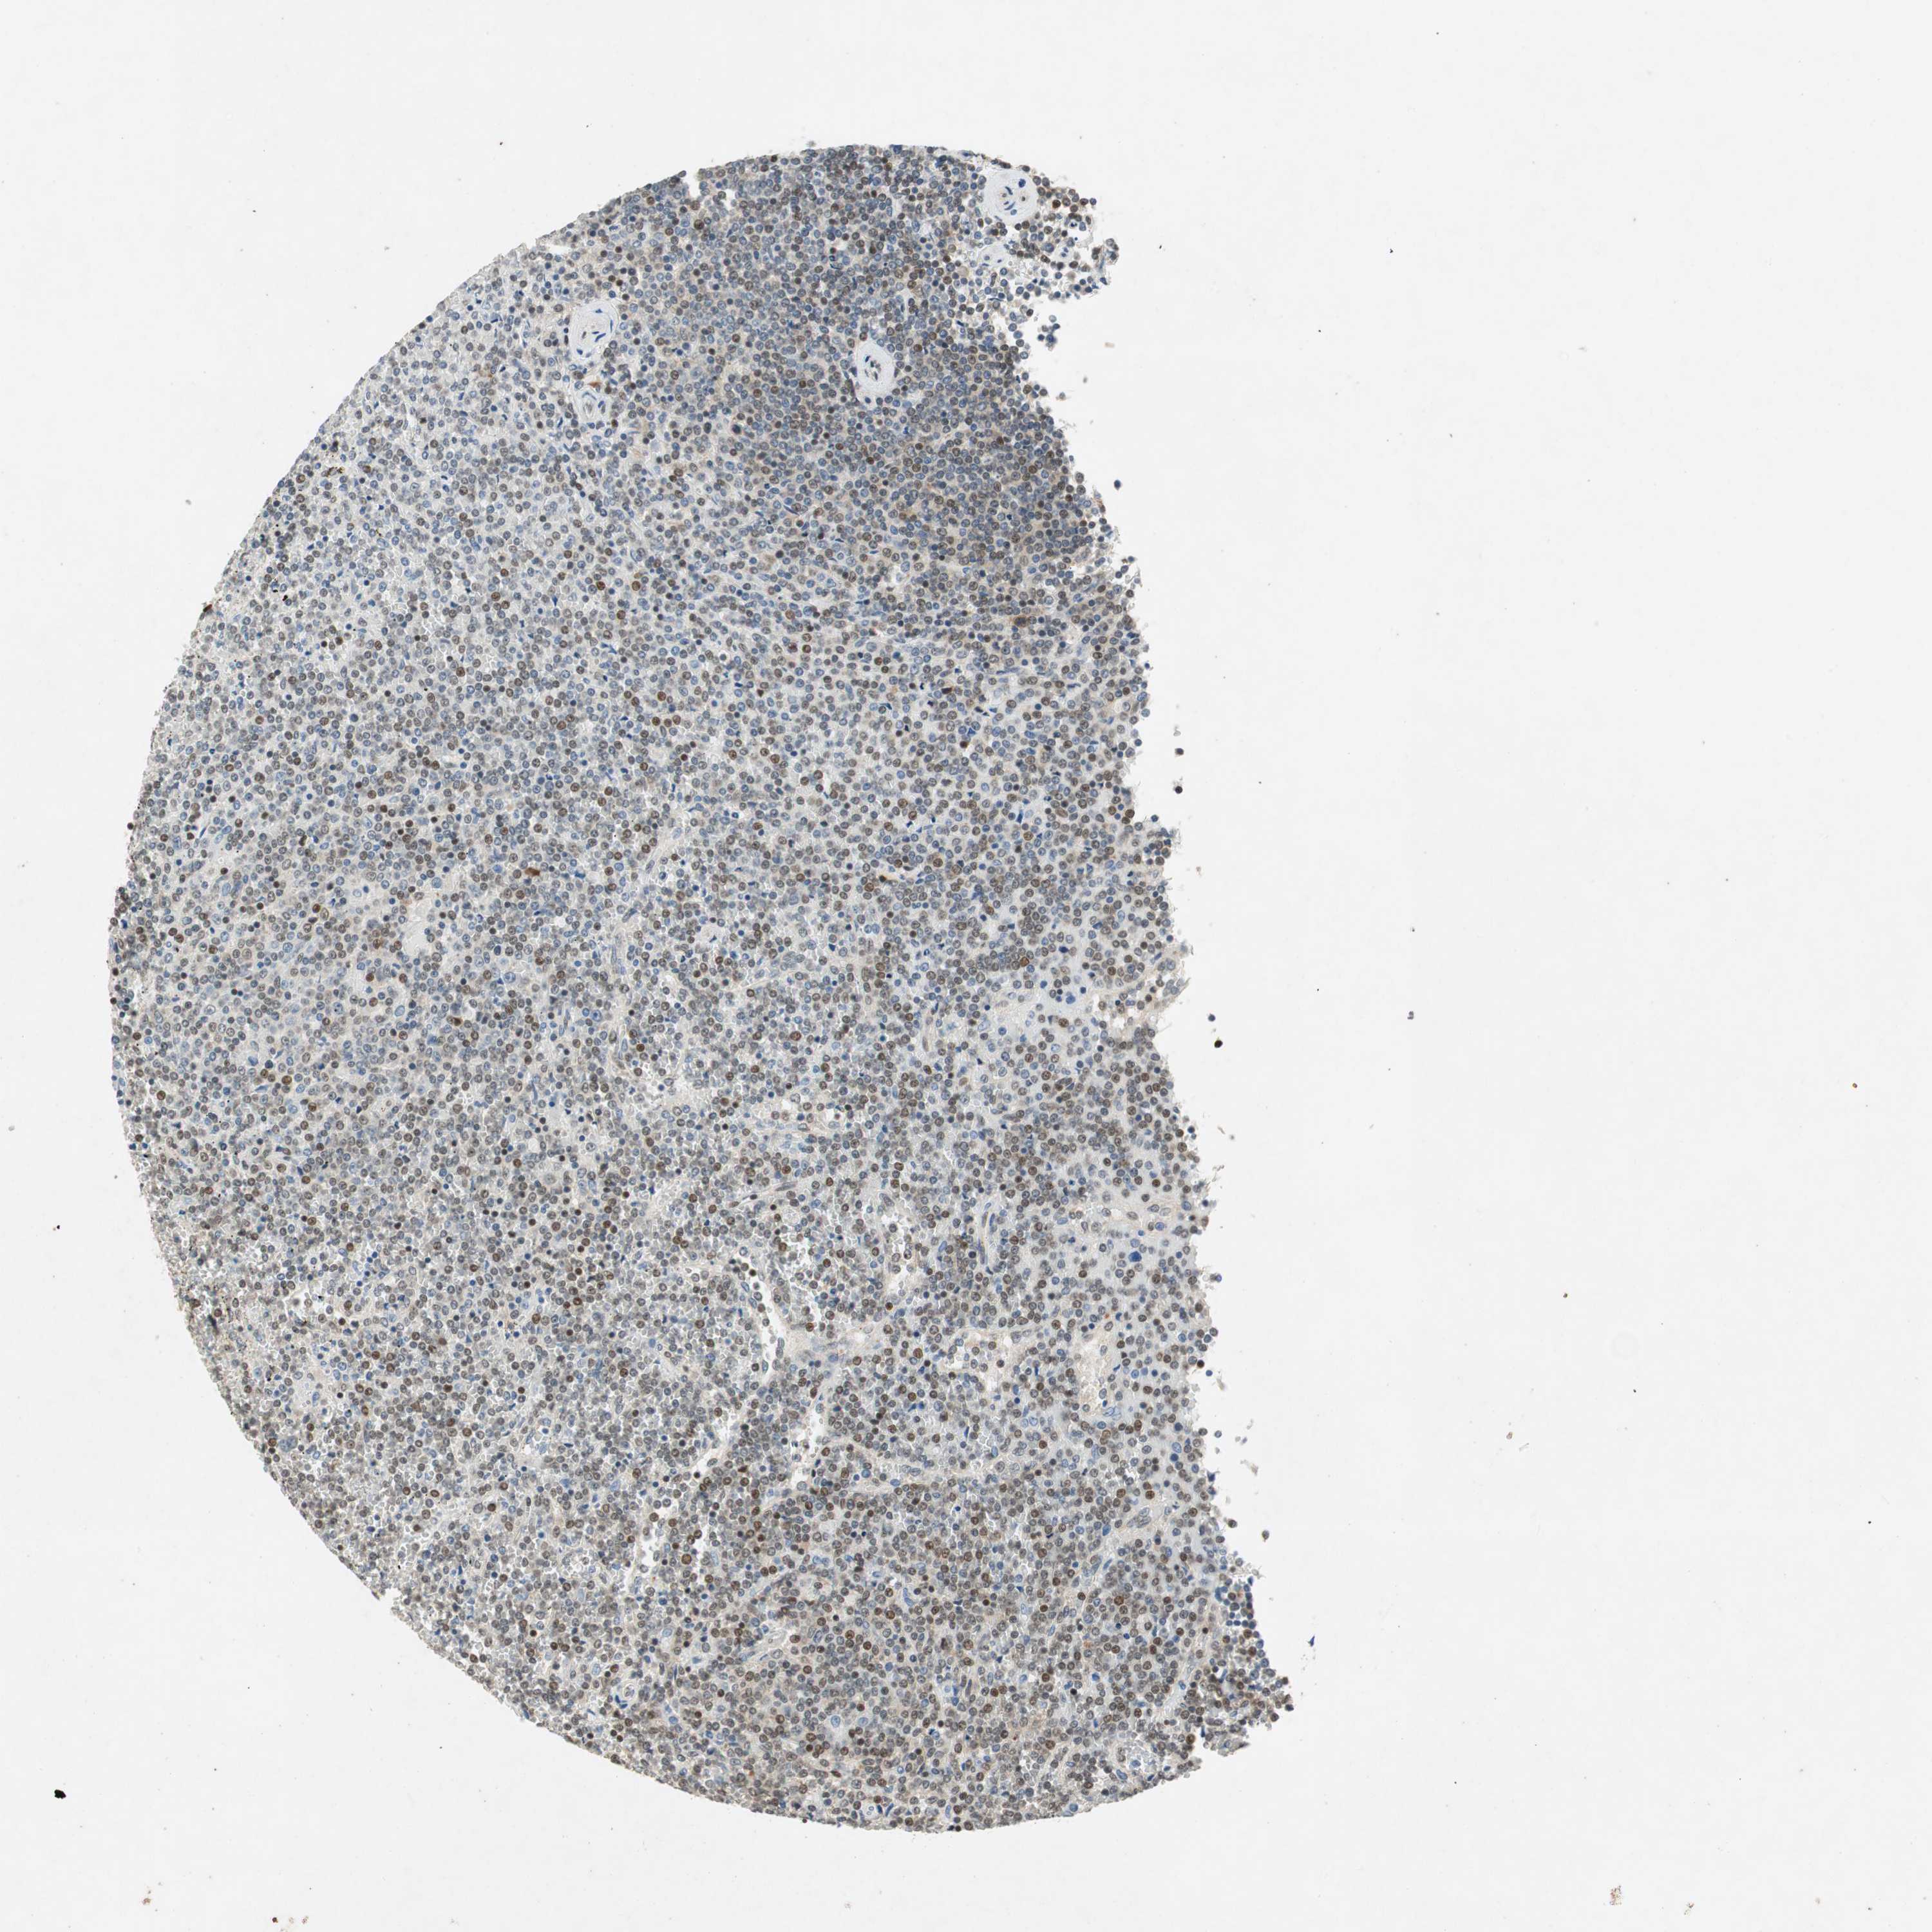

LYMPHOMA - Protein expressioni

A mouse-over function shows sample information and annotation data. Click on an image to view it in a full screen mode. Samples can be filtered based on level of antibody staining by selecting one or several of the following categories: high, medium, low and not detected. The assay and annotation is described here.

Antibody stainingi

Antibody staining in the annotated cell types in the current human tissue is reported as not detected, low, medium, or high, based on conventional immunohistochemistry profiling in selected tissues. This score is based on the combination of the staining intensity and fraction of stained cells.

Each image is clickable and will lead to virtual microscopy that enables deeper exploration of all samples and also displays staining intensity scores, fraction scores and subcellular localization as well as patient and tissue information for each sample.

Antibody HPA008959

Antibody HPA013195

Staining

High

Medium

Low

Not detected

Intensity

Strong

Moderate

Weak

Negative

Quantity

>75%

75%-25%

<25%

None

Location

Nuclear

Cytoplasmic/membranous

Cytoplasmic/membranous,nuclear

Hodgkin's disease, NOS

Malignant lymphoma, non-Hodgkin's type, Low grade

Malignant lymphoma, non-Hodgkin's type, High grade